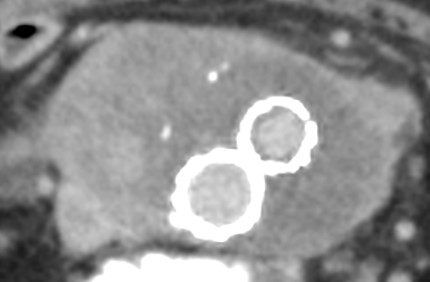

• 初回CT

• 22日後のCT

• 大動脈の右側、内膜石灰化よりも外側に、造影効果を有する占拠性病変を認める

• 両側肺野に微小な結節を多数認め、 1週間の経過で増大している